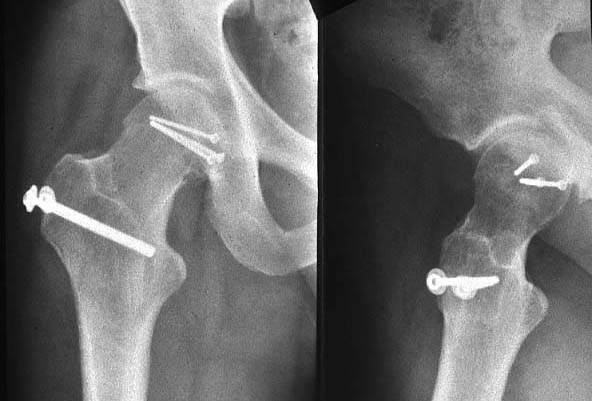

How femoral fractures are treated. Fracture healing can be attained in all femoral head fractures by using open reduction and screw fixation. However, the optimal surgical approach for the treatment of femoral head fracture remains controversial.

Wide treatment options for pipkin 1 femoral head fractures range from fragment excision, fixation following open reduction with internal fixation, or conservative treatment such as close reduction alone after fracture dislocation. The one exception to this is if there is a femoral neck fracture, at which point open reduction is almost certainly necessary. Controversies include the preferred surgical approach (anterior versus posterior) and whether to perform femoral head fragment excision or internal fixation.

Open reduction and internal fixation of the fracture of the femoral head is the treatment of choice for most young patients. The treatment of femoral head fractures associated with acetabulum fractures, pipkin iv fractures, presents difficulty as usually the femoral head. Surgical approach and fracture management is variable.

There are several surgical approaches and treatments for this difficult fracture. Sometimes screws are attached to a metal plate that runs down the femur. When surgical intervention is indicated, there are multiple approaches that can be successfully and safely used for definitive fixation.